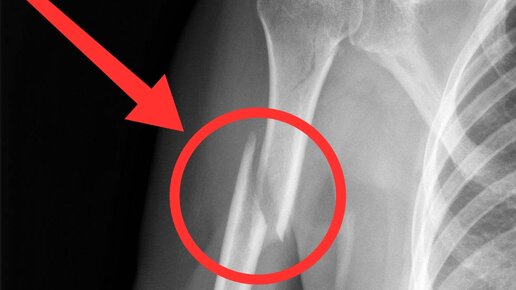

Всем привет, сегодня я с точки зрения профессионала хочу объяснить почему люди ломают руки или выворачивают их из суставов. Вообще армрестлинг один из самых безопасных видов спорта, но как не странно случаются переломы. Часто это скрученный перелом плечевой кости со смещением как показано на фото. При том что это ещё слабо, ведь кость может раздробиться что не даст вам перспективы заниматься этим в будущем. Но если это так опасно почему спортом ещё занимаются? Отвечу вопросом на вопрос. А вы видели...